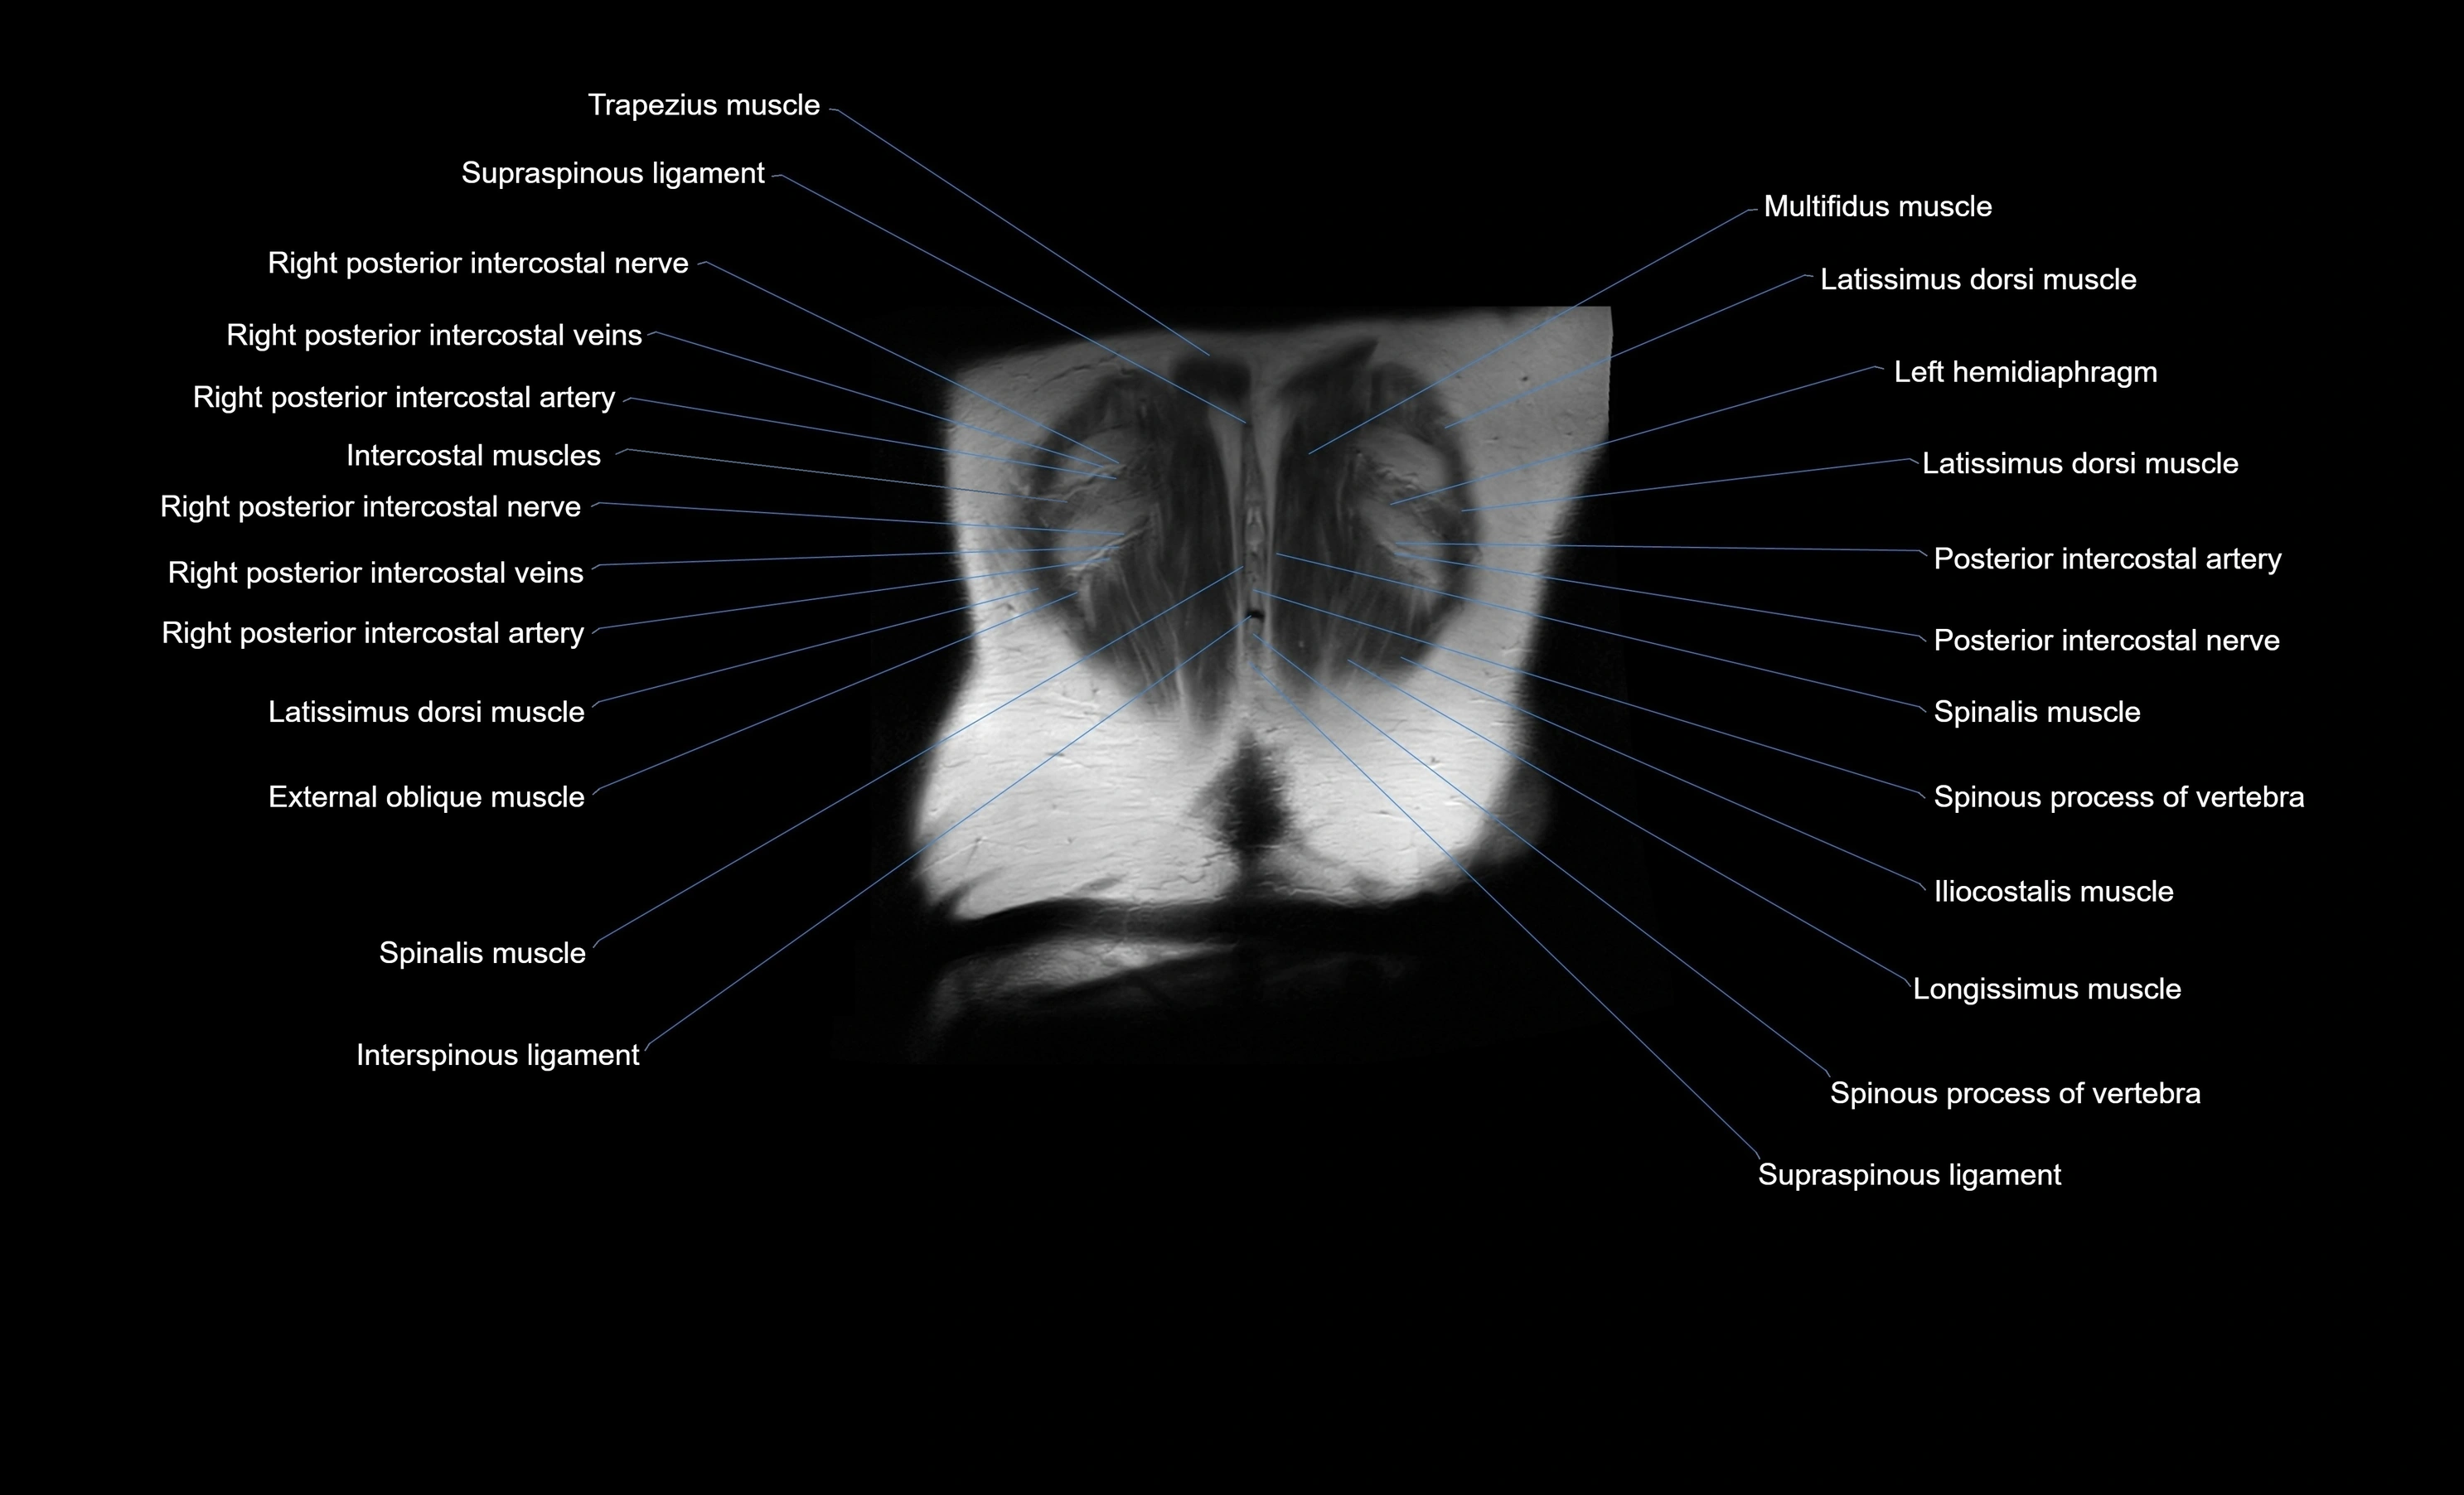

- Intercostal muscles

- Latissimus dorsi muscle

- Supraspinous ligament

- Interspinous ligament

- Spinous process of vertebra